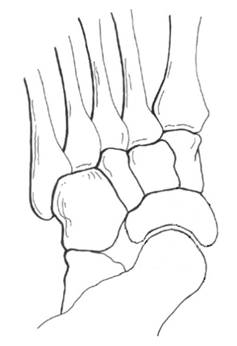

详细而全面的体格检查,是评价扁平足畸形的严重程度;是否发生合并症;以及是否伴有关节退行性改变最基本的诊断方法。扁平足畸形通常表现为跟骨外翻,前足的内翻以及外展,有时会合并距下关节半脱位。临床检查通常以坐位、立位和行走时检查最为重要。

X线是诊断扁平足的常用方法,其中负重正侧位X线是最为常用的诊断方法。通过测量多个角度来评价内侧纵弓的降低,前足的外展以及跟腱的挛缩程度。并根据这些指标指导临床治疗方式的选择。扁平足的X线测量指标主要有:1.负重侧位X线片:距骨第1跖骨角,跟骨倾斜角等。2.负重正位X线片:距舟覆盖角,距骨第2跖骨角等。其中侧位距骨第1跖骨角被认为是X线上评价扁平足最有意义的指标。除此之外还可应用SaltzmanX线及后足长轴位X线评价后足内外翻程度。